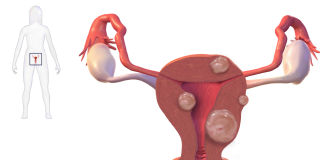

Fibromul uterin

Fibromul uterin reprezinta o masa celulara care se dezvolta la nivelul uterului. Acesta poate aparea la exteriorul uterului, in interiorul cavitatii uterine sau chiar...